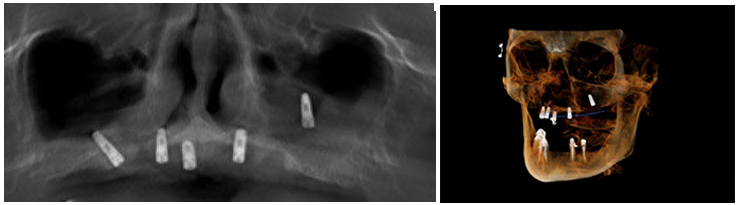

fig. 1-2